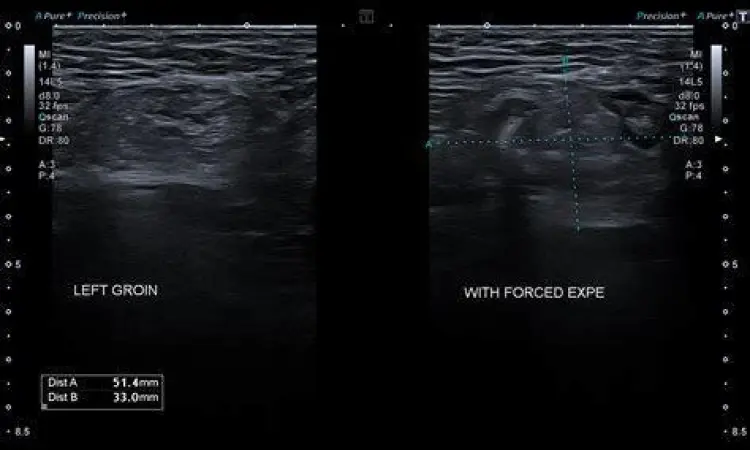

Hernia inguinalis terjadi ketika jaringan lunak, seperti bagian dari usus, menonjol melalui titik yang lemah atau robekan pada otot perut di area bawah. Kondisi ini lebih sering terjadi pada pria dibandingkan wanita. Karakteristik khas dari hernia adalah benjolan yang terlihat lebih jelas saat Anda batuk, mengejan, atau berdiri tegak, dan sering kali menghilang saat Anda berbaring telentang. Jika tidak ditangani, hernia dapat menyebabkan komplikasi serius seperti inkarserata atau strangulasi usus.

Diagnosis medis biasanya melibatkan wawancara medis mendalam (anamnesis) dan pemeriksaan fisik. Dalam beberapa kasus, dokter mungkin memerlukan pemeriksaan penunjang seperti USG inguinal, CT Scan, atau bahkan biopsi jika terdapat kecurigaan ke arah keganasan (kanker). Menunda pemeriksaan pada kondisi yang memerlukan tindakan bedah, seperti hernia strangulata, dapat berisiko fatal karena dapat menyebabkan kematian jaringan usus.